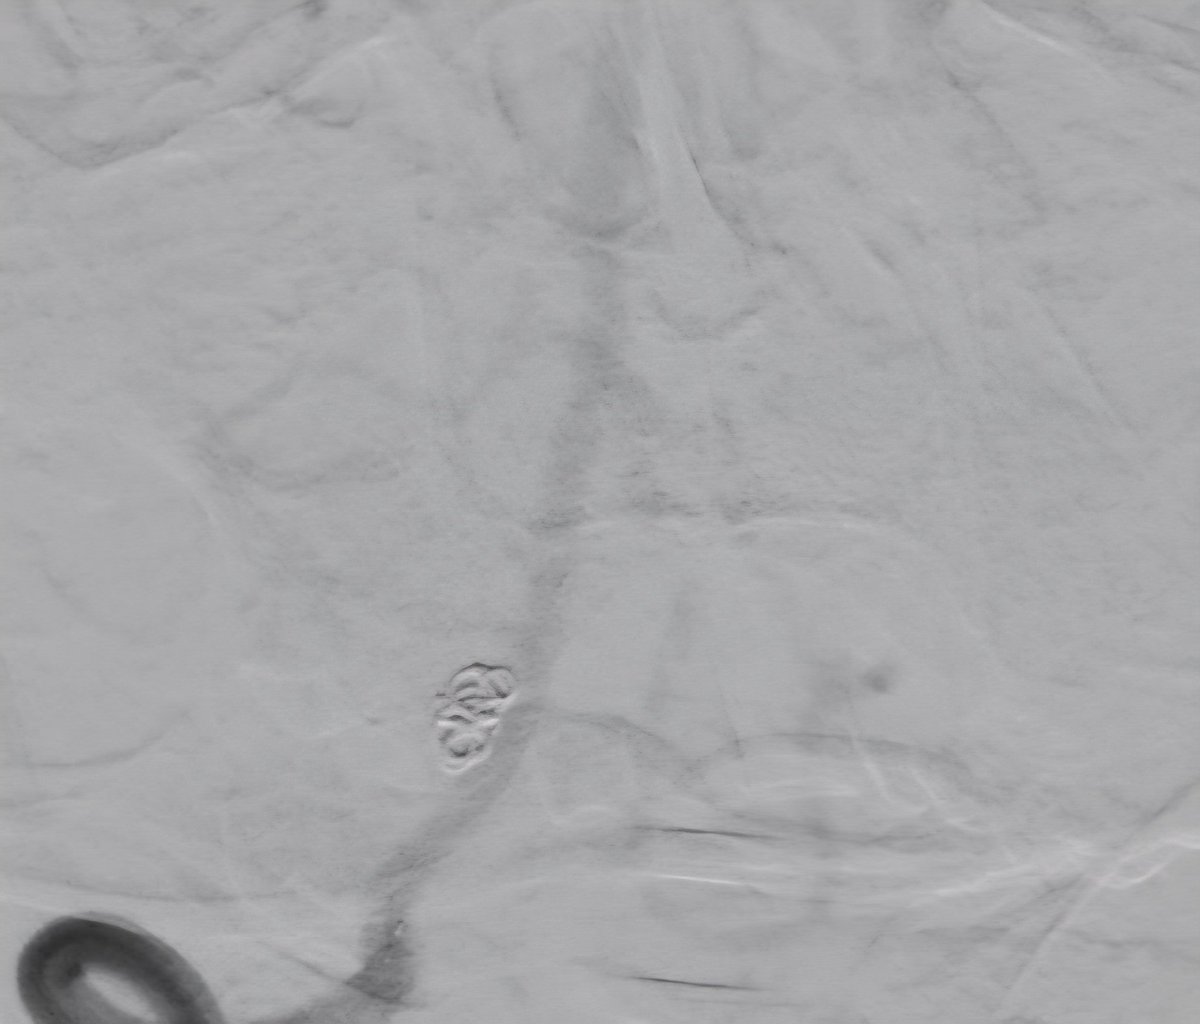

همه در یک بیمار. کاروتید راست:دایسکشن کاروتید چپ: تنگی شدید ورتبرال چپ: بسته شدن کامل از ابتدای شریان ورتبرال راست: دایسکشن و آنوریسم. درمان: استنت کویل در ورتبرال راست و نیز استنت کاروتید چپ. ادامه درمان با ضد پلاکت.